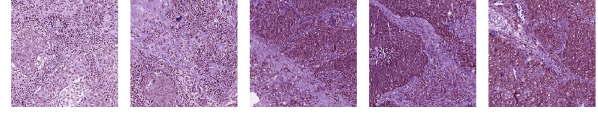

| Cluster 2 () |

![]() |

| Cluster 40 () |